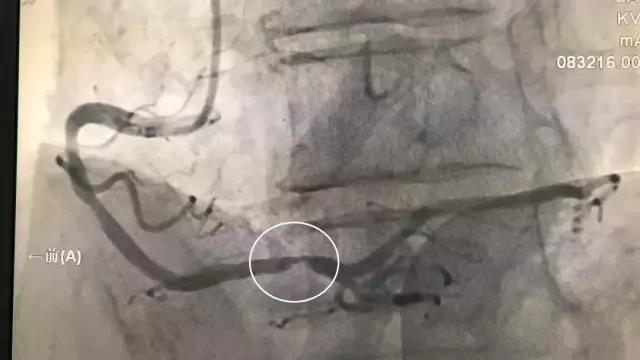

上图,右冠状动脉中远段严重狭窄(见划圈处),考虑血管闭塞后再通,仍需要介入干预